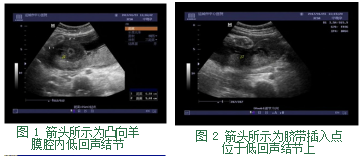

胎盘绒毛膜血管瘤为圆形或类圆形肿块,常邻近脐带入胎盘处,与正常胎盘界限明显,多位于胎儿面,但也可发生于胎盘任何部位 [4]。

超声是产前发现此疾病的唯一有效手段,临床上仅有50% 的诊断率。其典型超声声像图:胎盘中见一界限清楚实性包块,与胎盘关系密切,常凸向羊膜腔,内部回声以低回声或蜂窝样无回声较多见,内有较大血管时可有花纹状钙化条斑 [4]。其超声声像易发现,易诊断,但在实际工作中易漏诊与误诊 [5]。

胎盘绒毛膜血管瘤当瘤体较大,与脐带入口紧邻时,则胎儿可能出现一些不良情况,此时产科医生会相对被动,处理不及时有可能妊娠结局不良甚至导致医患纠纷。希望通过此病例的学习,基层医院的临床及超声医师能很好地掌握胎盘绒毛膜血管瘤的超声声像图改变,以及可能引起的不良结局,及早诊断,及早告知可能风险,加强监测,减少不良结局的发生, 见图 1-10。